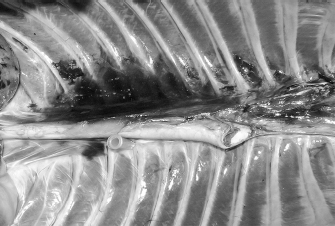

Fig. 1. Polyurethane foam injection at the level of the left caudal TPVS in a cat cadaver. The Tuohy needle has been used to probe the space, avoiding any damage to the parietal pleura (asterisk). The tip of the needle in at the level of the thirteenth left costovertebral joint.

Five cat and five dog cadavers of various breeds and weights were studied within 5 hours after euthanasia for clinical reasons. Animals with a history or evidence of thoracic pathologies or trauma were excluded from the study. The thoracic cavity was accessed by bilateral costotomy. The heart, lungs, and thoracic tract of the trachea were removed, whereas the normal anatomy of the dorsal mediastinum was preserved. Adopting the same technique described for the preliminary phase, the subpleural compartment of the TPVS was then probed, and the polyurethane foam was slowly injected (Fig. 1) until its complete spread (approximately 10 minutes). The probes were then gently withdrawn, and the cadavers were left in position until the foam had completely expanded and hardened (20 minutes). The spread of the foam was studied by anatomical dissection. Different color stains were used to distinguish between the sides injected. The cranial and caudal borders of the TPVB were defined as the farthest vertebra reached by the colored foam for each side and direction.